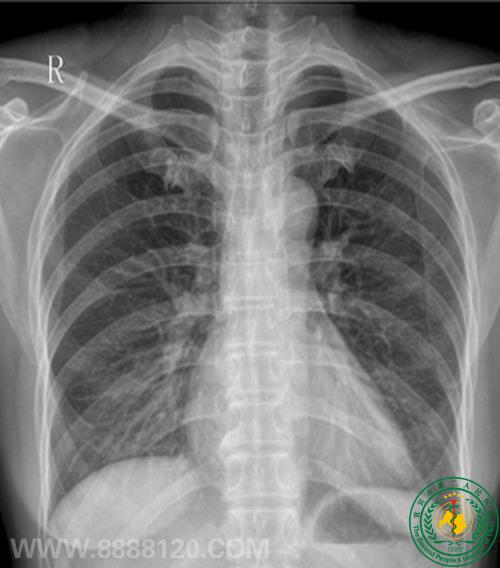

病例51病员无身体不适,例行体检。

DR 未见异常,CT示左肺固有上叶一磨玻璃密度样结节,直径约1.6cm,考虑为肿瘤性病变可能。术后病检:符合原位腺癌(细支气管肺泡癌),支气管断端未查见肿瘤累及。